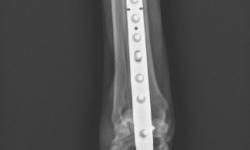

Pacient č.: 1. - rtg po operaci.

Pacient č.: 2. - pooperační rtg.

Pacient č. 3. - pooperační rtg.

Pacient č. 3. - po operační rtg 2.